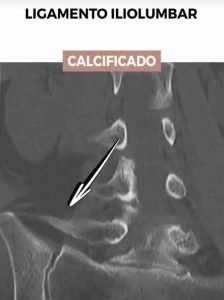

Calcificación del ligamento iliolumbar

La calcificación del ligamento iliolumbar es otra condición que puede agravar el síndrome iliolumbar, manifestándose a través de rigidez y dolor crónico en la zona lumbar. Esta afección ocurre cuando el tejido ligamentoso, que normalmente es flexible, comienza a endurecerse debido a la acumulación de calcio.

Esto limita seriamente el movimiento y puede causar un dolor considerable al realizar actividades cotidianas o incluso en reposo. La identificación temprana de la calcificación es vital para implementar tratamientos que puedan aliviar los síntomas y mejorar la flexibilidad, implicando a menudo un enfoque combinado de fisioterapia, medicación y, en casos específicos, procedimientos quirúrgicos dirigidos.

Esta imagen de T.A.C. muestra una clara calcificación en el ligamento iliolumbar, una condición indicativa de síndrome iliolumbar avanzado